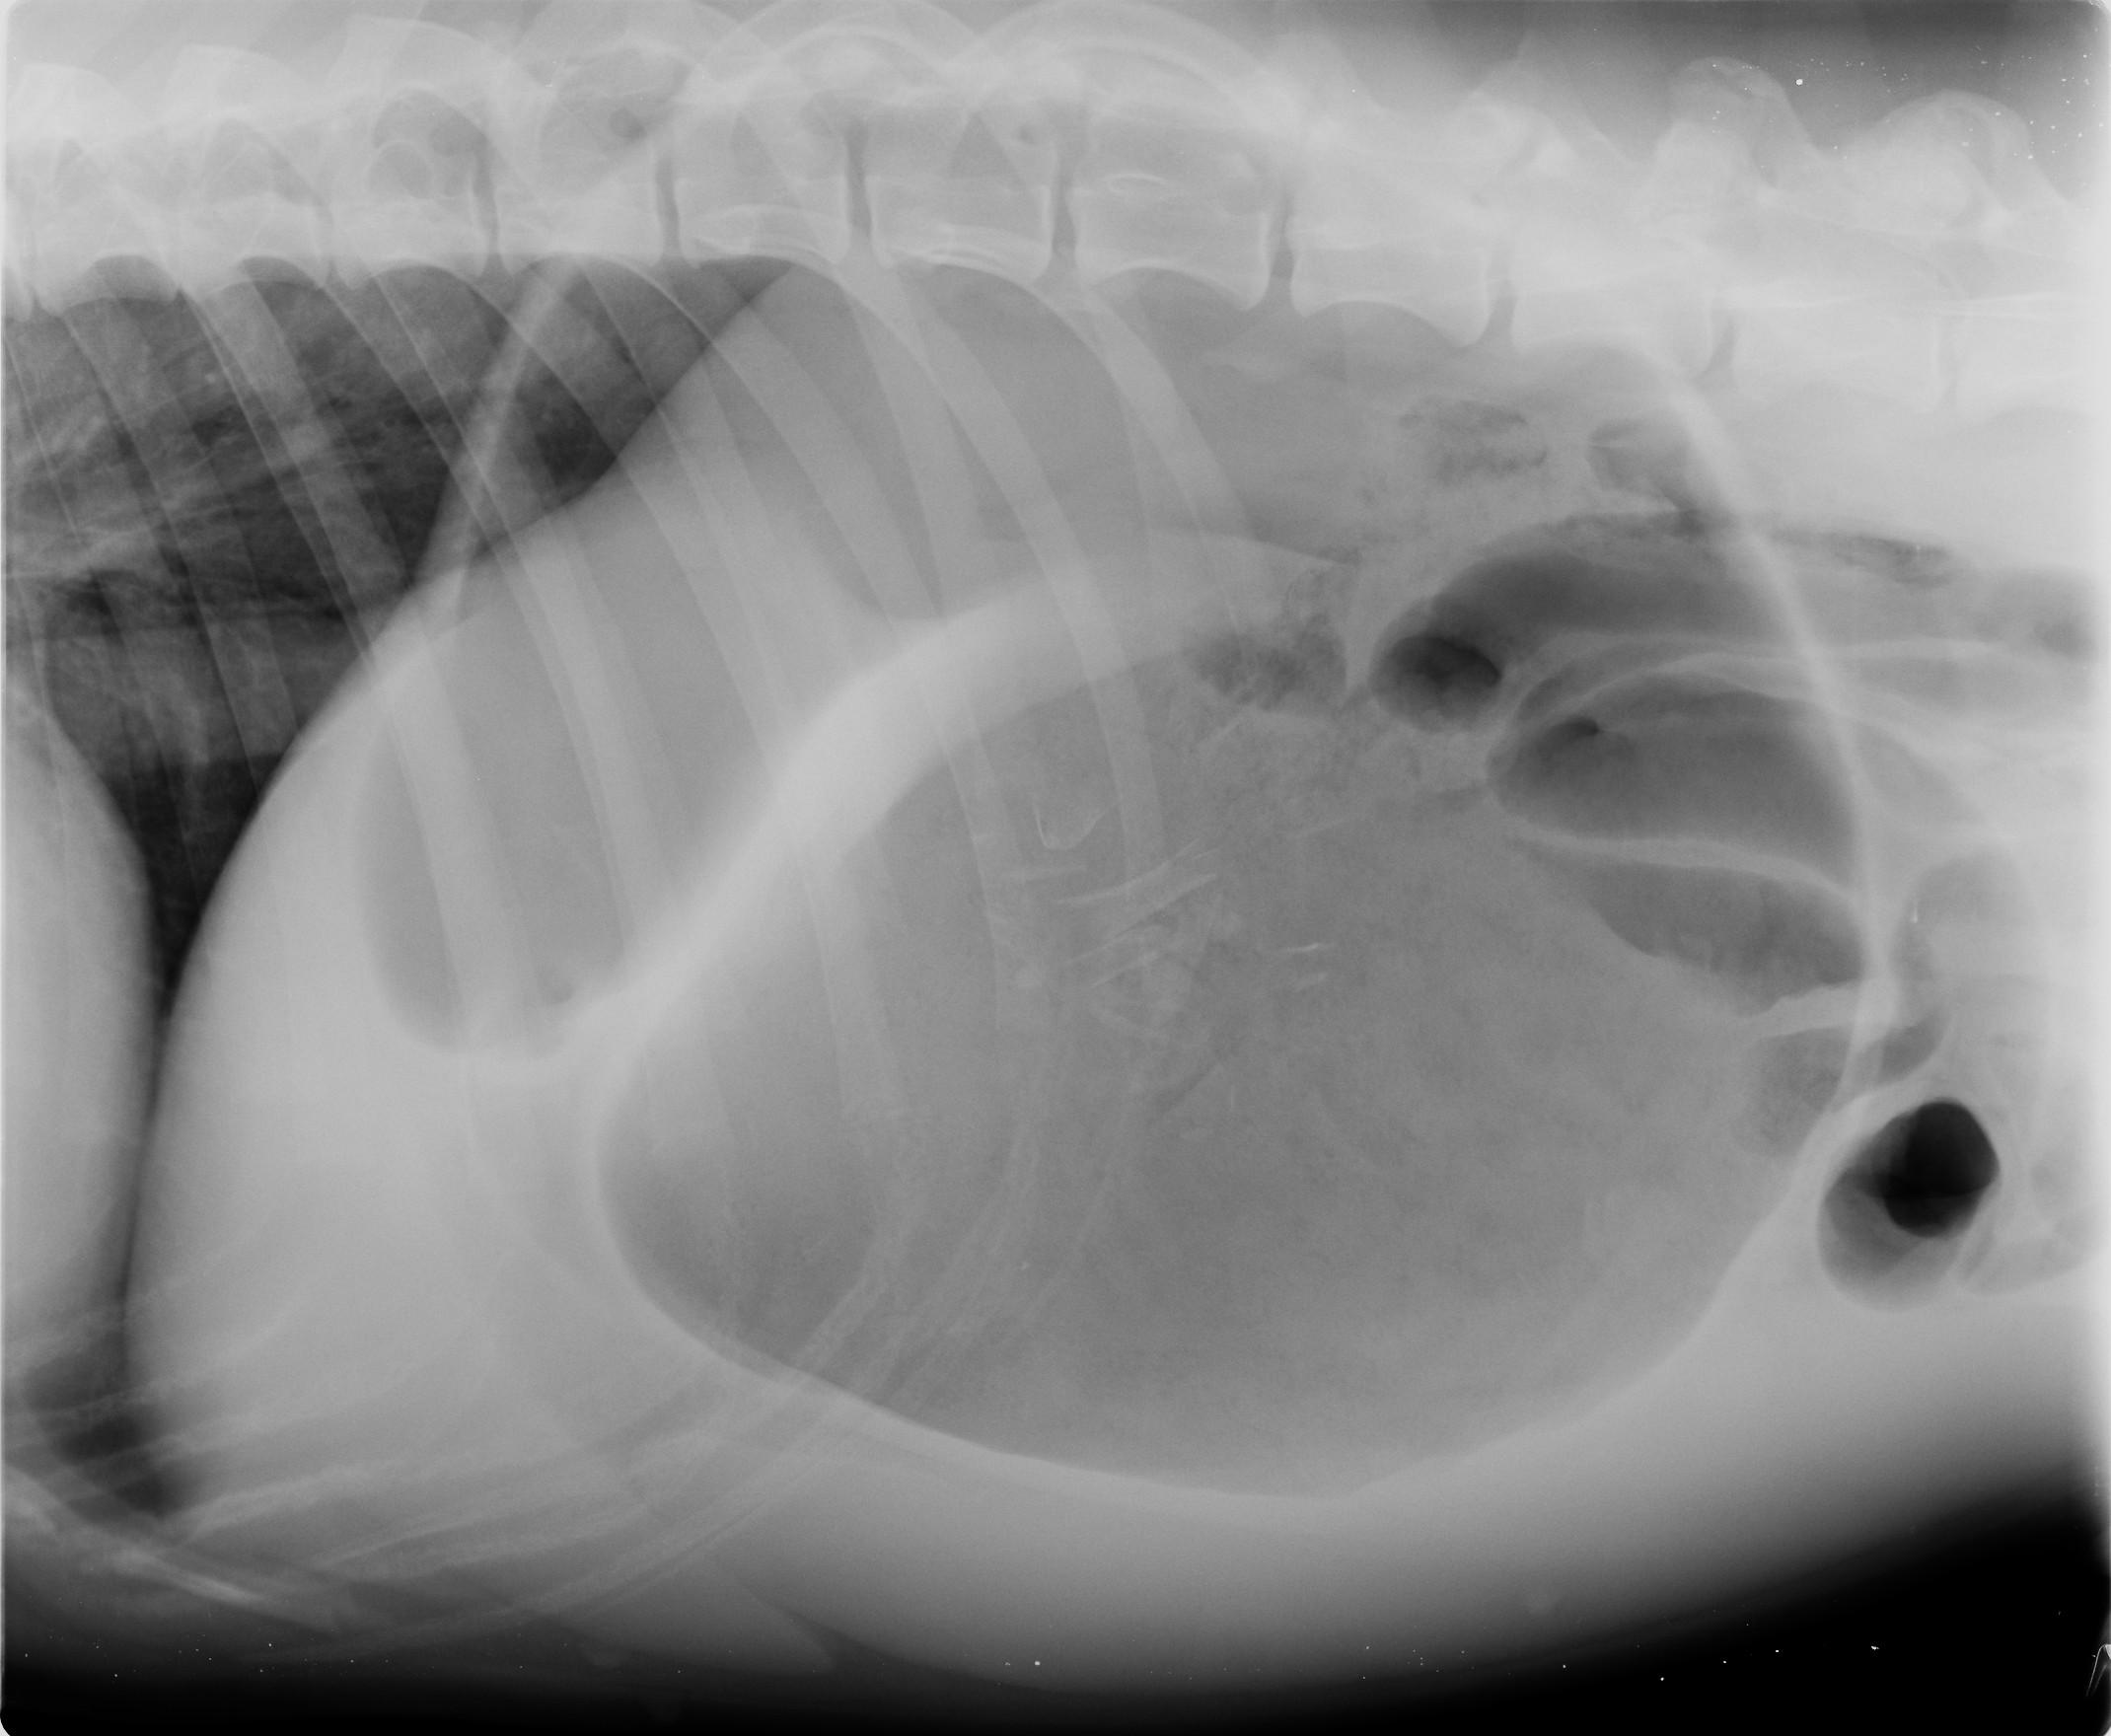

Pour rétablir une oxygénation adéquate des organes, une ou plusieurs perfusions sont mises en place (en fonction de la taille du chien), l’estomac est décomprimé par trocardisation si nécessaire (on place une aiguille dans le haut de l’estomac pour laisser sortir l’air emprisonné et décomprimer l’abdomen). Ensuite une radiographie est réalisée pour permettre de différencier une « simple dilatation » d’une réelle torsion. En cas de dilatation sans torsion, l’animal est tranquillisé et une sonde est placée dans son estomac par la gueule et l’osophage. S’il y a torsion, une chirurgie est nécessaire, en URGENCE, pour détordre l’estomac. A cette occasion, on suturera la paroi de l’estomac à la paroi costale, afin d’éviter toute nouvelle torsion (gastropexie).